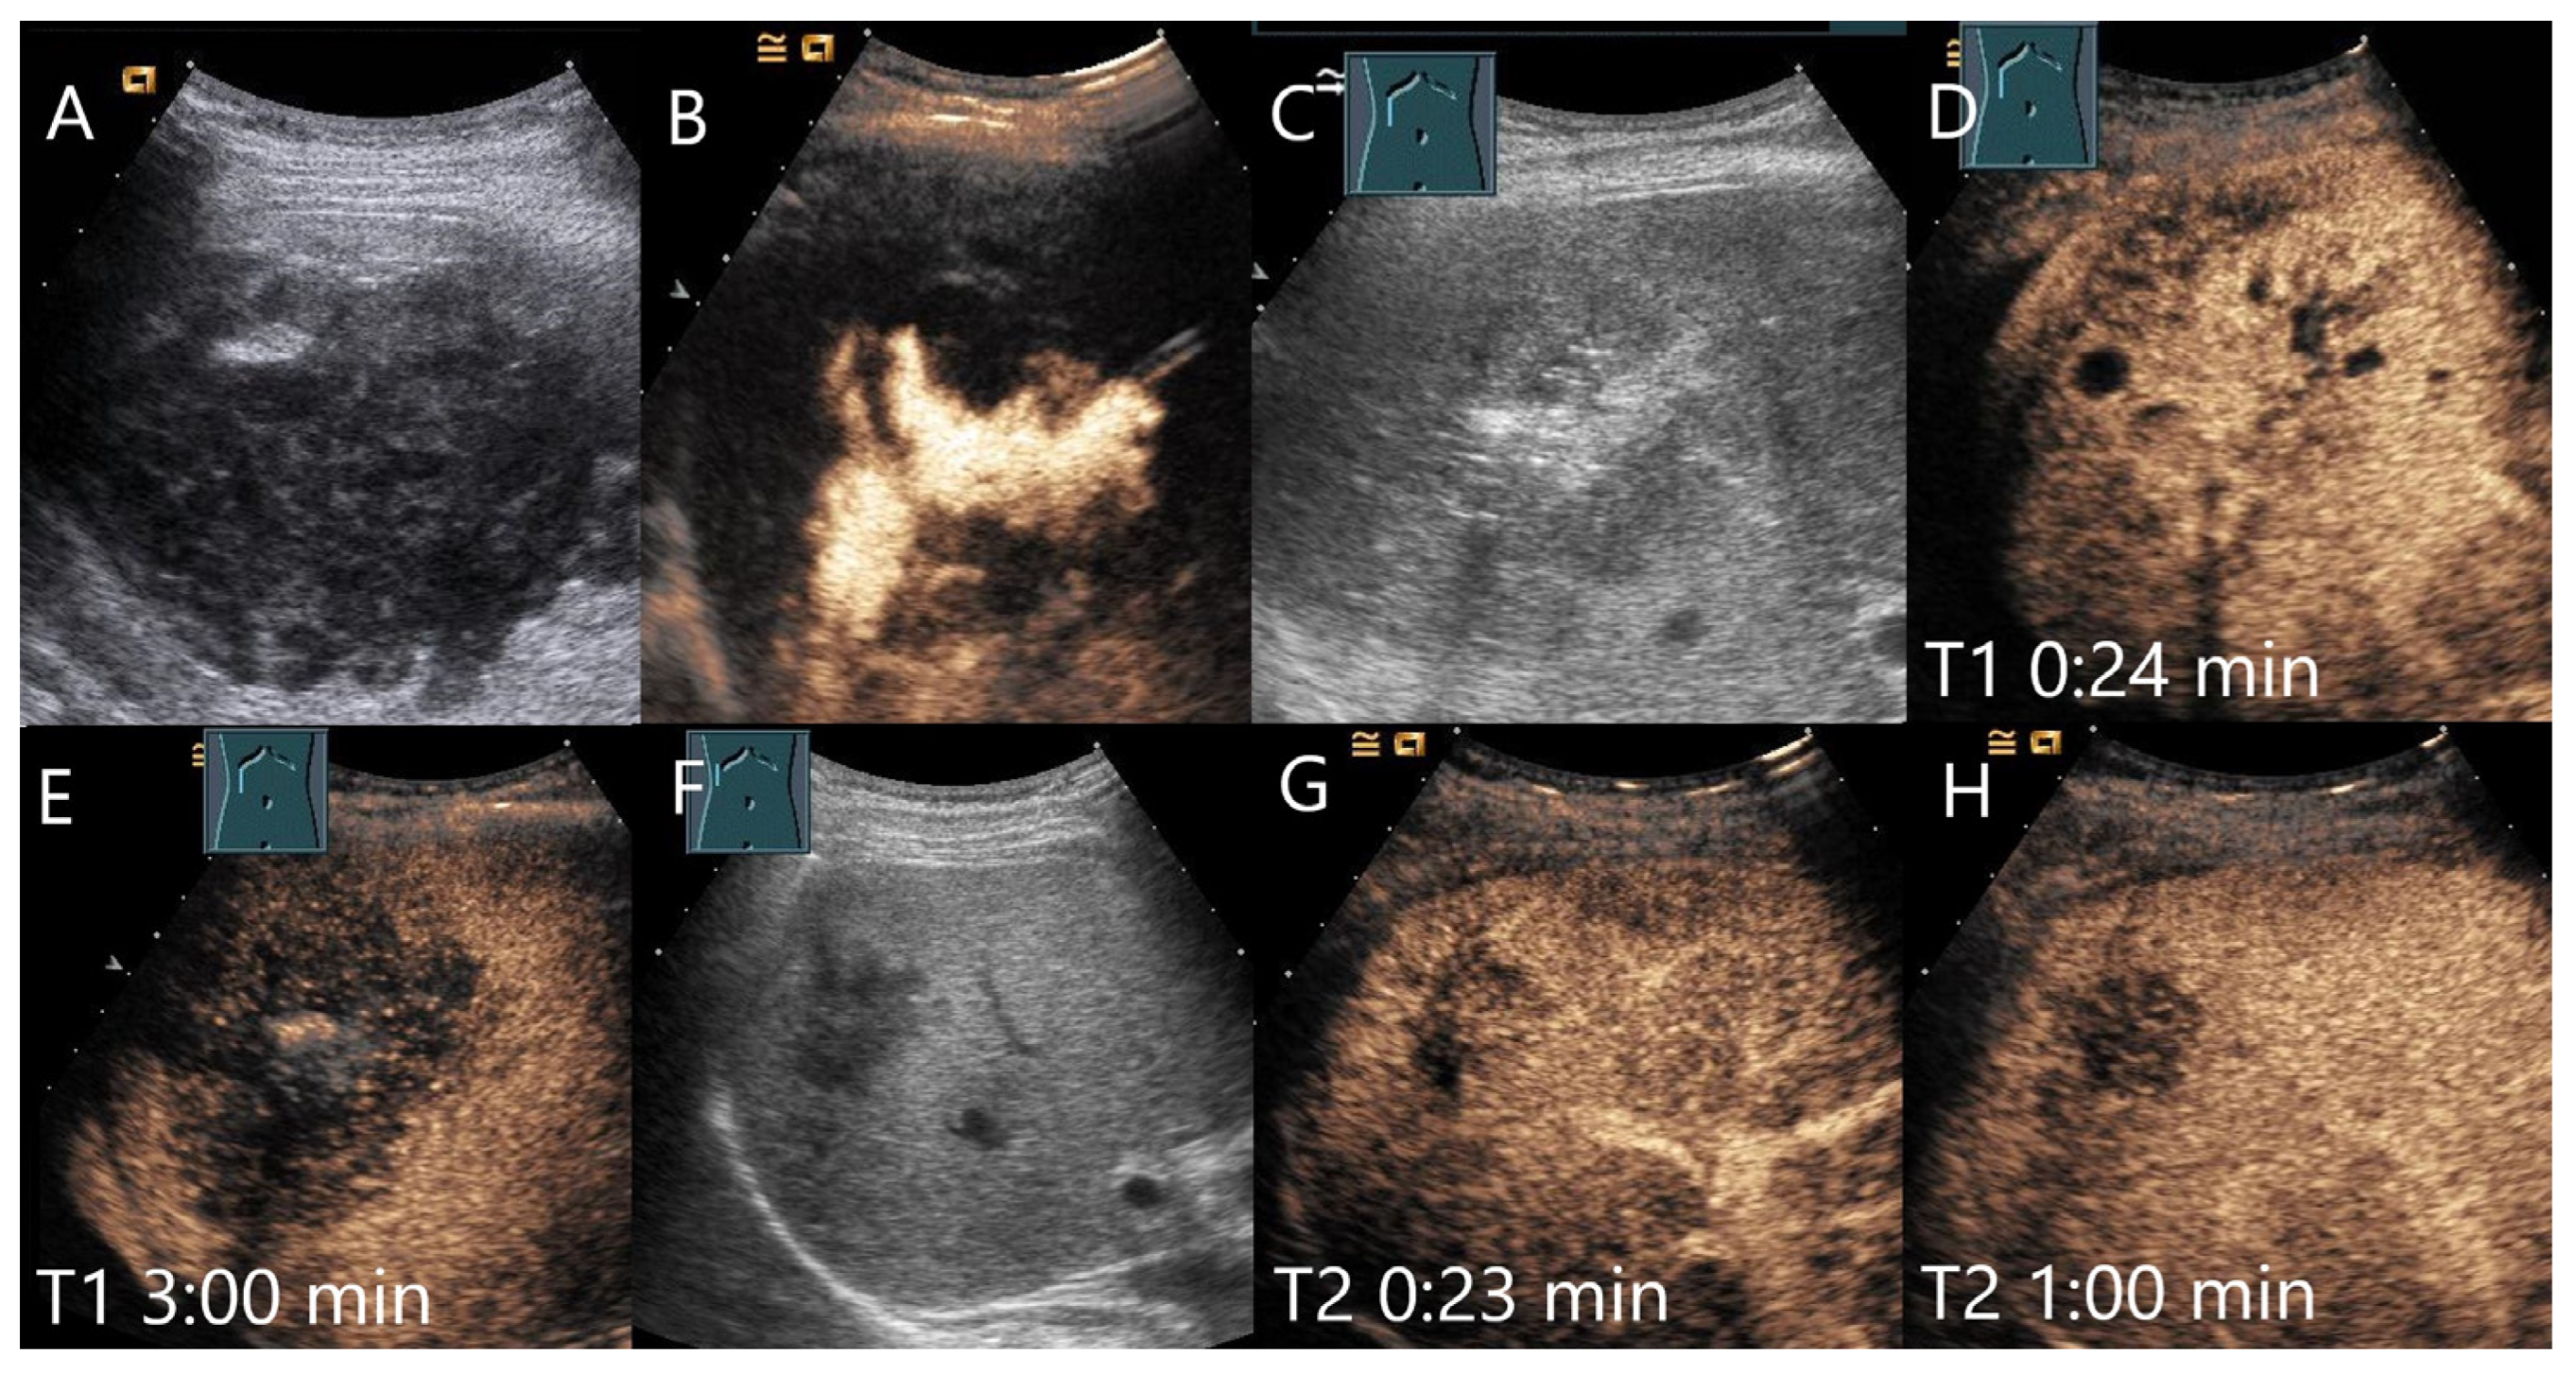

| Hemangioma | Hyperechoic, beyond liver veins, hypoechoic in steatosis and with shunts. | Peripheral globular enhancement, centripetal filling. Rapid homogeneous filling in shunt hemangiomas. | Hyperenhancement and isoenhancement. | Permanent video loops with destruction of the UCA bubbles and slow refill. Fibrosis. |